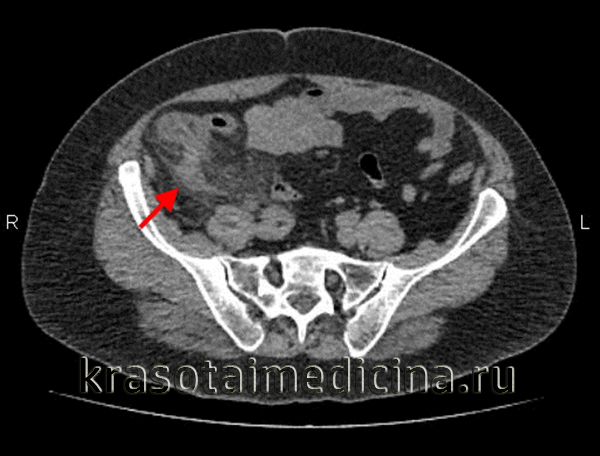

КТ ОБП. Выраженное утолщение червеобразного отростка до 1,5 см с наличием воспалительных изменений периаппендикулярной клетчатки